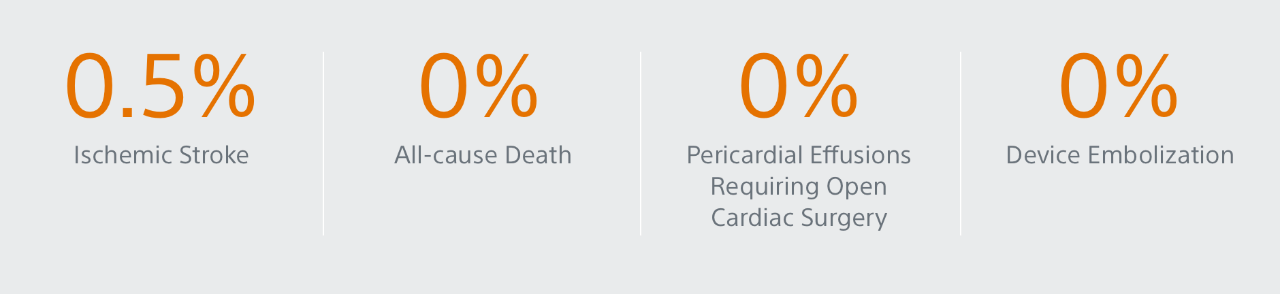

ICE LAA

Study Design

ICE LAA is a multi-center study with core-laboratory adjudication, this analysis reported the 45-days results from 100 real-world WATCHMAN FLX patients from 7 European centers.

Summary of the Results

- 100 real-world, European WATCHMAN FLX patients (from 7 implanting centers)

- 100% Device Success (Implantation of WATCHMAN FLX without in-hospital mortality)

- 100% Technical Success (Successful deployment and release, no conversion to TEE and effective closure of LAA at implant [no leak <5mm])

- 0% Conversion to standard TEE during implant

- 0% leak >5mm

- Key 45-days safety outcomes:

- 1% all-cause death

- 0% all stroke

- 0% pericardial effusion

- 0% DRT

- 0.% device embolization

- 3,1% major bleeding (BARC 3/5)

Outcomes with WATCHMAN FLX using Intracardiac Imaging: Results from ICE LAA